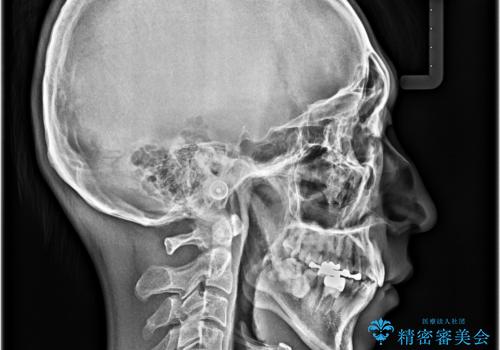

精密検査の結果、上下左右の小臼歯4本を抜歯し、そのスペースに前歯を後方へ移動させる矯正治療をご提案しました。

治療期間は約2年。

少しずつ前歯を後ろに下げていくことで、横顔のラインが整い、口元の“出っ張り感”が解消。

治療後には「自然に笑えるようになった」と嬉しいお声をいただきました。